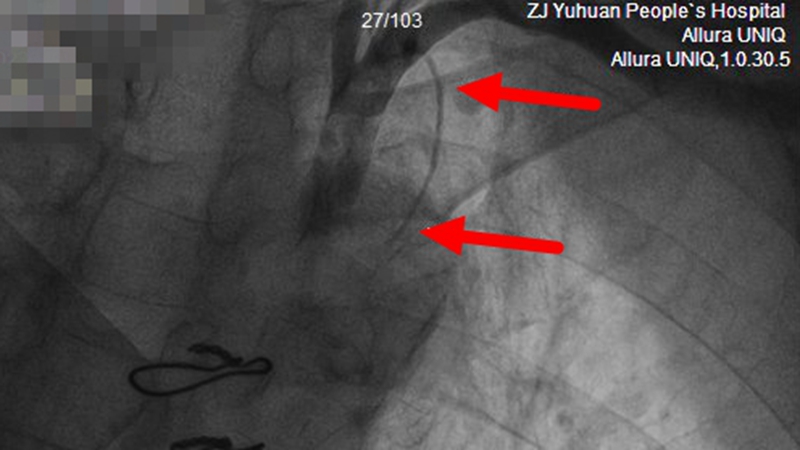

果不其然,造影发现,王伯的左内乳动脉——前降支“桥血管”明显细小、远端闭塞,这是最重要的一条“桥血管”。

【术前,左侧内乳动脉纤细 远端完全闭塞】